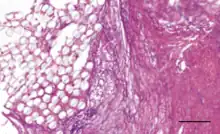

The Ligament Advanced Reinforcement (LARS) is a leading artificial ligament in ACL repair surgery. They are made of polyethylene terephthalate (PET).[3] They consist of an intraosseous and an intra-articular portion. The intraosseous section consists of longitudinal fibers bounded by a knitted transverse structure. This knitted structure can help prevent deformation and abrasion.[5][11] The intra-articular portion is made of longitudinal fibers pretwisted at a 90 degree angle. This section is designed to resist fatigue and promote tissue ingrowth.[5] Leeds Keio ligaments consist of a polyester mesh structure. It seeks to mimic the mechanical properties of the native ACL. The porous nature of the ligament can promote tissue ingrowth which has been shown to improve mechanical properties.[5] The PGA Dacron artificial graft consists of 75% braided biodegradable polyglycolic acid and 25% permanent Dacron thread.[11] The Kennedy LAD artificial ligament is made of polypropylene ribbons. It is designed to promote tissue ingrowth and the progressive transfer of load onto the new ligament.[10]

Coatings have been added to artificial ligaments to improve their biocompatibility. 58S bioglass and hydroxyapatite coatings have been shown to improve osseointegration and cellular activity in vitro and in animal studies[3] when deposited onto PET ligaments using the soaking method.[2][3] Hydroxypropyl cellulose surface treatments have been shown to improve osseointegration for PET ligaments in animal studies.[2] Uncoated PET is hydrophobic, so coatings are designed to improve hydrophilicity.[3] Hyaluronic acid coatings can reduce hydrophobicity and have been shown to reduce scar tissue formation and inflammation in vivo.[3] Hyaluronic acid and chitosan composite coatings can be deposited onto artificial ligament surfaces by the layer-by-layer technique, and they have been shown to enhance new bone formation at the ligament interface in mice.[9] The chitosan is used to reduce hydrophobicity and improve osseointegration and mineral deposition, while the hyaluronic acid promotes cell differentiation and growth.[9] Poly(sodium styrene sulfonate) coatings have been shown in animal studies to improve knee functionality and mimicry of the native ACL.[2][13]